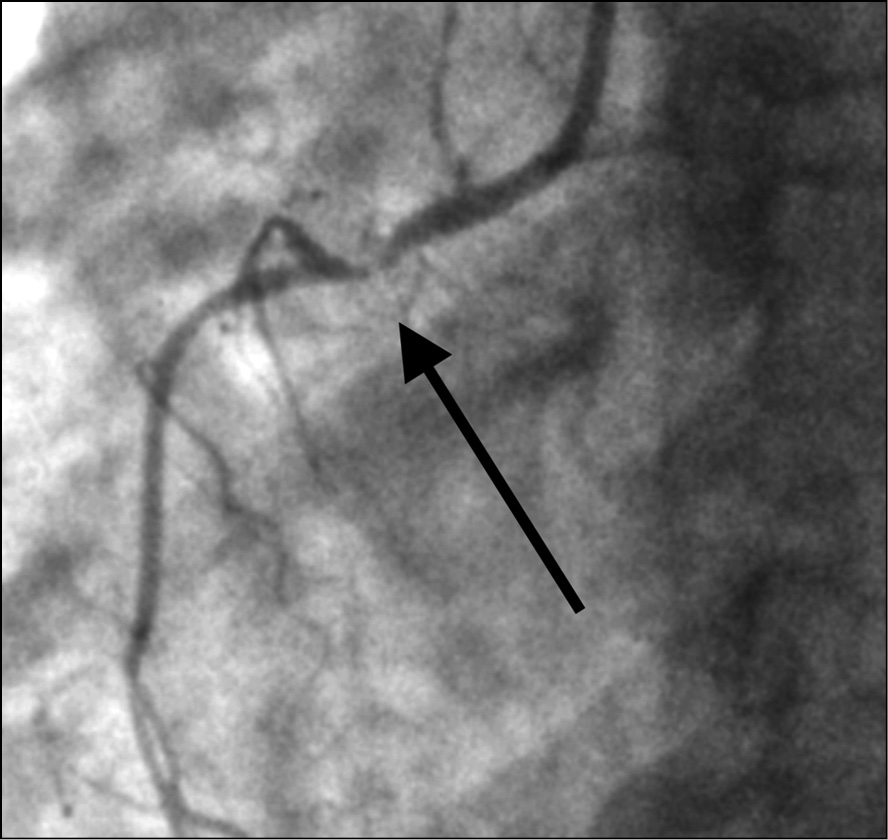

Выполнена коронарография трансрадиальным доступом, на которой выявлено многососудистое поражение коронарного русла: субокклюзия средней трети передней нисходящей артерии (рис. 2), субокклюзия устья первой ветви тупого края (рис. 3), субокклюзия проксимальной части правой коронарной артерии (рис. 4). Диаметр правой коронарной артерии менее 2 мм. Левый тип кровоснабжения миокарда. Тяжесть поражения коронарного русла по шкале Syntax 1 [3] составила 13 баллов (легкая). Рекомендованный метод реваскуляризации миокарда по шкале Syntax 2 [4] — аортокоронарное шунтирование (53,6 балла для чрескожного коронарного вмешательства и 28,6 баллов для аортокоронарного шунтирования).

Рис. 4. Пациентка Б., 64 года, с острым коронарным синдромом, находящаяся на программном гемодиализе: при коронарографии трансрадиальным доступом выявлена субокклюзия проксимальной трети правой коронарной артерии (указана стрелкой)